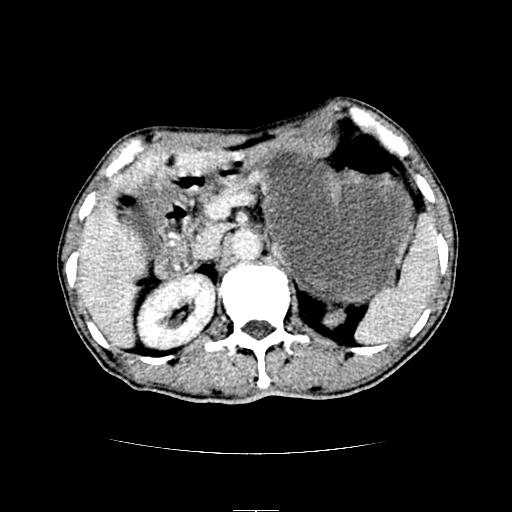

左上腹胃、脾及胰腺间巨大囊性占位性病变,内见多数薄隔,有轻度强化,明显占位效应。左肾见一小囊肿。

考虑:1、左上腹巨大囊肿(可能来源于胰腺)。

2、左肾小囊肿。

左上腹胃、脾及胰腺间巨大囊性占位性病变,内见多数薄隔,有轻度强化,明显占位效应,胰腺及左肾结构清楚,明显向后下方推压 移位。左肾见一小囊肿.多考虑:1 网膜巨大囊肿。2 左肾小囊肿。

1胃脾胰之间一巨大囊性影,胃明显向前推移,胰体尾部似肥大,考虑囊性影来源于胰腺(假性囊肿?)2左肾小囊肿。

左上腹胃、脾及胰腺间巨大囊性占位性病变,其内见多数薄隔,有轻度强化,明显占位效应。左肾见一小囊性变。

左肾囊肿;网膜巨大囊肿。